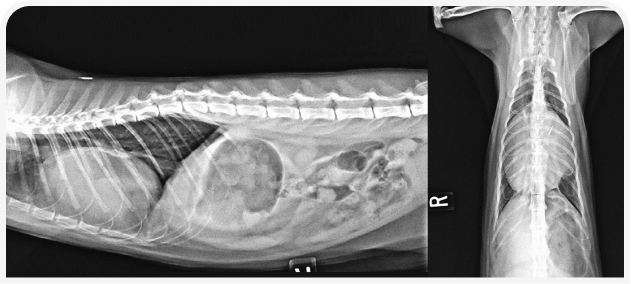

У котят шумы в сердце обнаруживают относительно часто, и при их диагностике и лечении врач должен придерживаться систематического подхода. Решающую роль в определении следующих шагов играют тщательный сбор анамнеза и тщательное клиническое обследование. Рентгенография грудной клетки может быть полезна при первоначальном обследовании, но для установления окончательного диагноза причин шума требуется эхокардиография; показанием к ее проведению считают шумы IV степени или выше, либо клинические признаки по результатам физикального осмотра. Терапию определяют исключительно на основании окончательного диагноза.